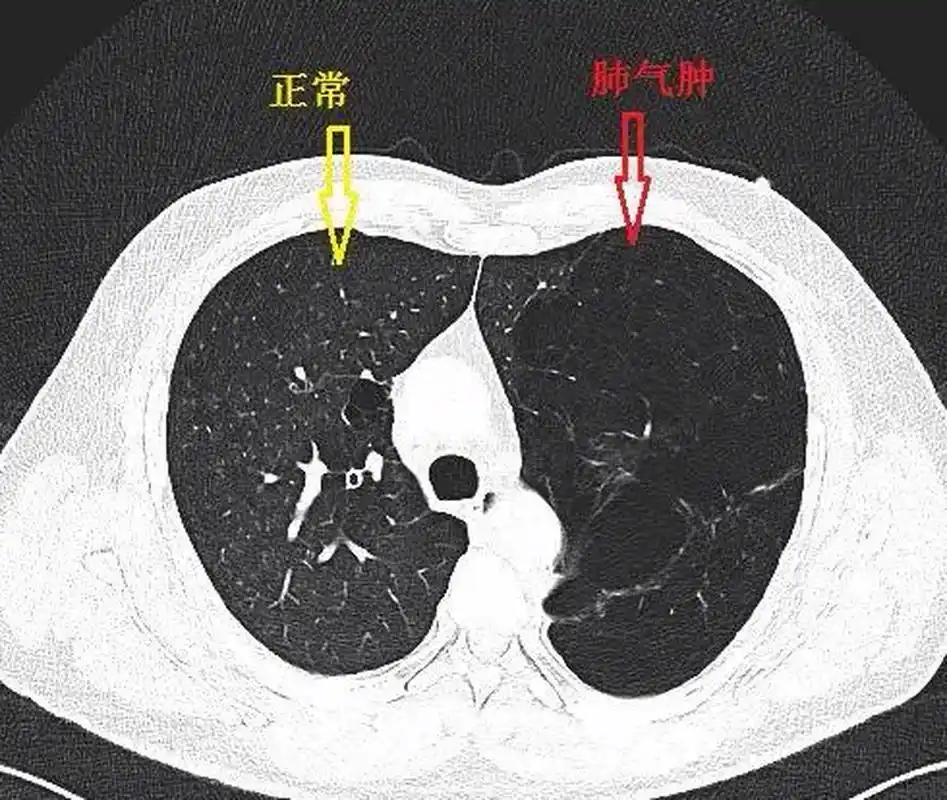

肺大泡肺气肿的区别是什么?